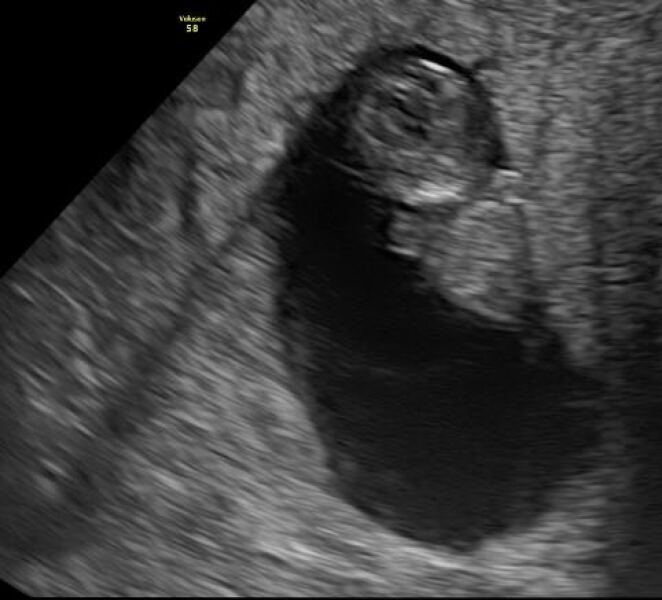

CharlotteRae · 12/07/2025 21:03

Ahhh all was fine, measuring 9 weeks 2 days xx

4w5d test still not dark solid

whatdoyouthink123456 · 12/07/2025 21:50

@CharlotteRae😍 amazing! Only 2 days difference!